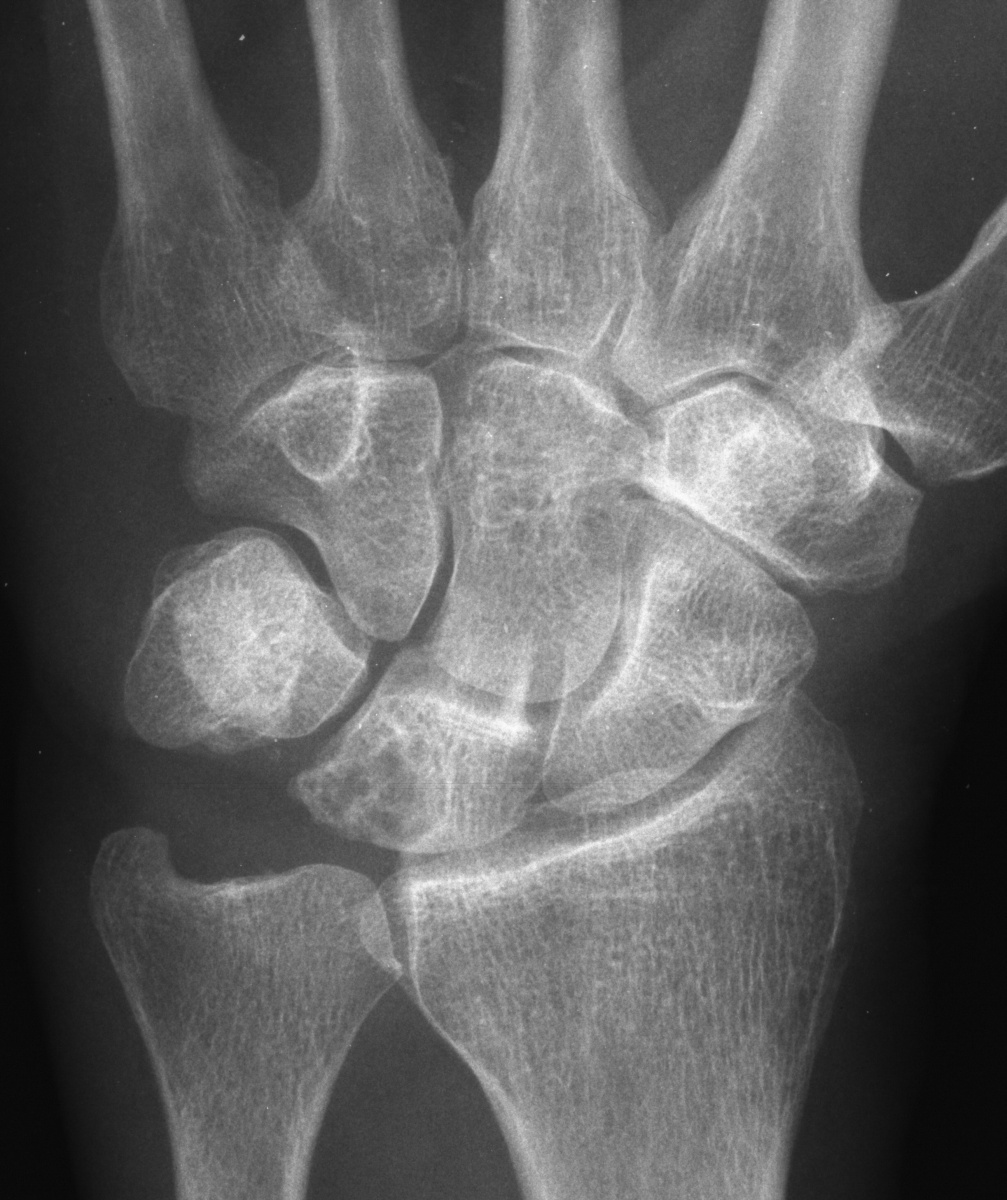

Clinical Example: Lunate Cyst

This imaging series was obtained for evaluation of a one month history of painful pronosupination in an active 85 year old man whose daily exercises include pushups.